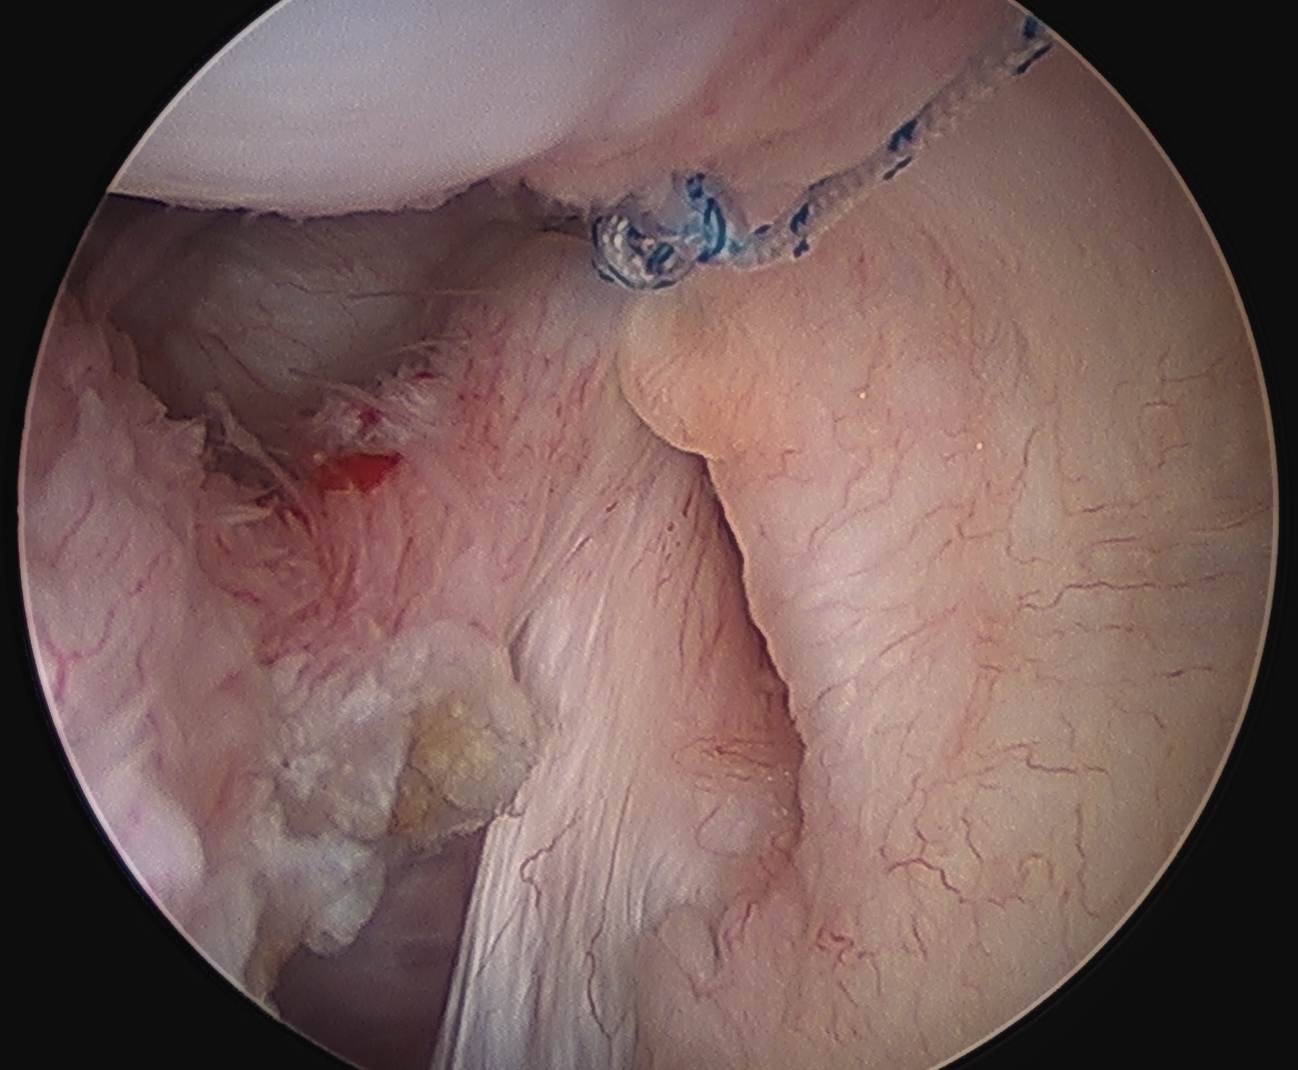

Arthroscopy

Capsule tear anteriorly, extending up into humeral insertion

Side to side suture repair +/- HAGL repair

Side to side repair of capsular tear

Intact anterior labrum with capsular tear, axillary nerve seen below capsular tear in axillary recess